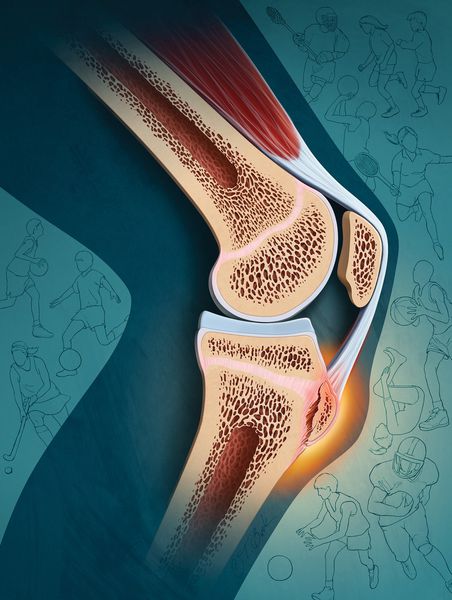

Болезнь Осгуда-Шлаттера характеризуется, как мы уже говорили, развитием неинфекционного воспаления кости и её некрозом. Бугристости на большеберцовых костях располагаются в их верхних частях, потому для этой патологии характерны боли в коленных суставах. Воспалительным процессом, как правило, бывают затронуты обе кости (одностороннее поражение – явление более редкое). Иногда происходит сочетанное поражение большеберцовых костей и позвоночника. Местом возникновения заболевания является связочный аппарат коленей, в связи с чем оно может осложниться появлением тендинита.

Нагрузки на незрелые бугристости приводят к сбою в их питании. Вследствие дефицита питательных веществ образуется некроз костной ткани с разрушением и разрывами последней, что и приводит к появлению воспаления.

Из-за постоянных микротравм обрывается много капилляров, но кровоснабжение в большеберцовой кости не нарушается. Это приводит к кровоизлиянию, и у пациентов появляются синяки диаметром 1–3 см. Если не прекратить тренировки, начинается отрыв надкостницы вместе с костным фрагментом (апофизом). На месте отрыва формируется костная мозоль и бугристость становится заметной [10] [12] .